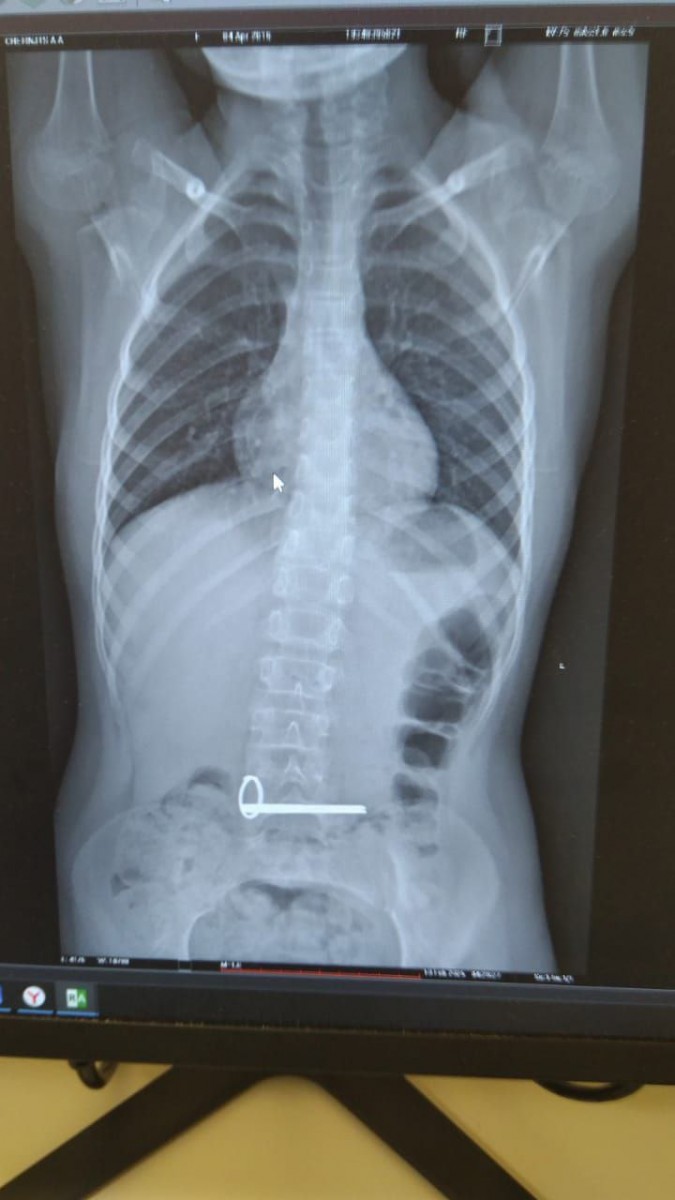

Ночью в отделение экстренной помощи ОДКБ поступил ребёнок с инородным телом в желудке. На снимке, сделанном во время обследования, отчётливо видны два ключа.

Эндоскописты без осложнений извлекли ключи из желудка ребёнка. Операция прошла под наркозом.